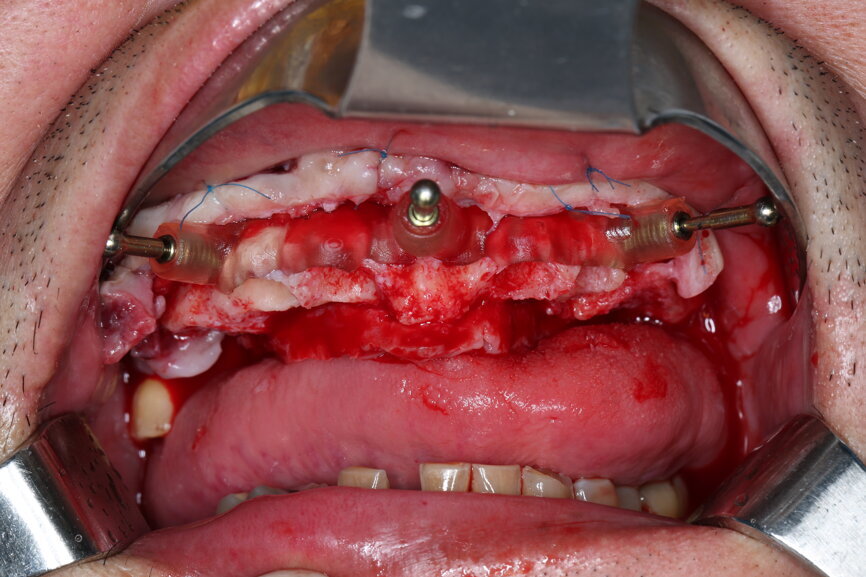

On the day of surgery, we prepared for the surgical protocol provided by the implant planning software, which guided us on the drilling sequence and the use of the appropriate instruments for the implant bed preparation (Figs. 30a & b). After the fixation pins had been allocated, teeth #17, 16, 15, 13, 12, 22, 23 and 24 were atraumatically extracted and alveolectomy was performed using a bone reduction guide (Figs. 31–36). Four implants (Straumann BLX; regular base; diameter: 4.5 mm; length: 12.0 mm) were placed, two straight implants in the anterior and two titled implants in the posterior. All the implants were stabilised to a torque of 50 Ncm (Figs. 37–43), and the SRAs were placed on top. The SRAs on the posterior implants had an angulation of 30° (diameter: 4.6 mm; gingival height: 3.5 mm) and on the anterior implants an angulation of 17° (diameter: 4.6 mm; gingival height: 3.5 mm; Figs. 44 & 45).

The bite registration guide was fixed with pins, and the open-tray impression copings were placed on the SRAs of the anterior implants, which were fixed with the guide using flowable composite and then sent to the laboratory (Figs. 46–50). Afterwards, we checked the CAD/CAM temporary restoration which had been designed and milled before surgery (Fig. 51), and protective caps were placed on the SRAs, followed by bone grafting using cerabone granules (botiss biomaterials) with a 1–2 mm grain size in the extraction sockets and suturing (Figs. 52–54).